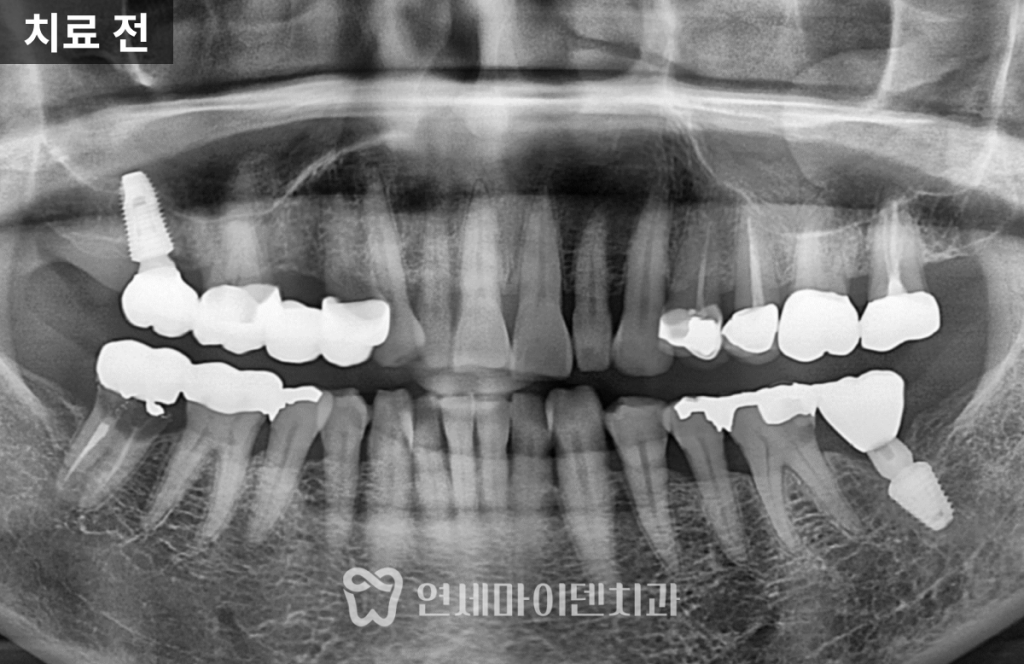

재신경치료&임플란트 증례: 해외 거주 환자

이번 포스팅에서는 2개월 후 출국을 앞둔

해외 거주자 환자의 임플란트 및 신경치료 케이스를 중심으로

짧은 일정 안에서도 효과적인 치료가 가능했던

치료 과정을 소개해드리겠습니다.

환자분의 왼쪽 아래 어금니(#36)는

기존 금 인레이 아래로 2차 충치가 발생한 상태였습니다.

통증이 동반되었으며, 충치 깊이가 신경에 도달해

신경치료가 불가피한 상황이었습니다.